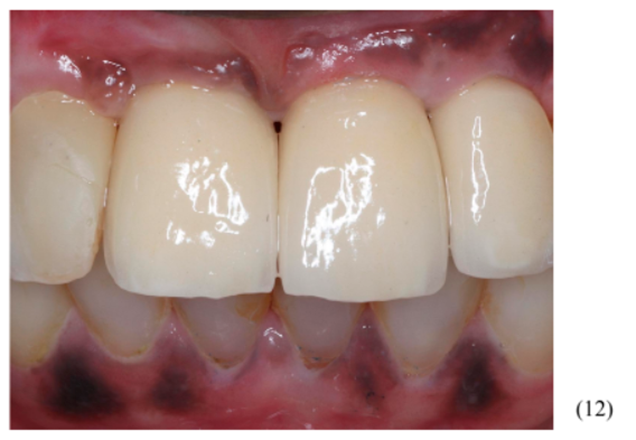

Utilizamos três munhões do tipo Ideale – Implacil De Bortoli de altura 3.3×2.5×4 mm para confecção das próteses do tipo parafusada (imagens 10 e 11). A foto final foi no acompanhamento de seis meses, onde podemos observar ótima estabilidade do tecido peri-implantar (imagem 12).